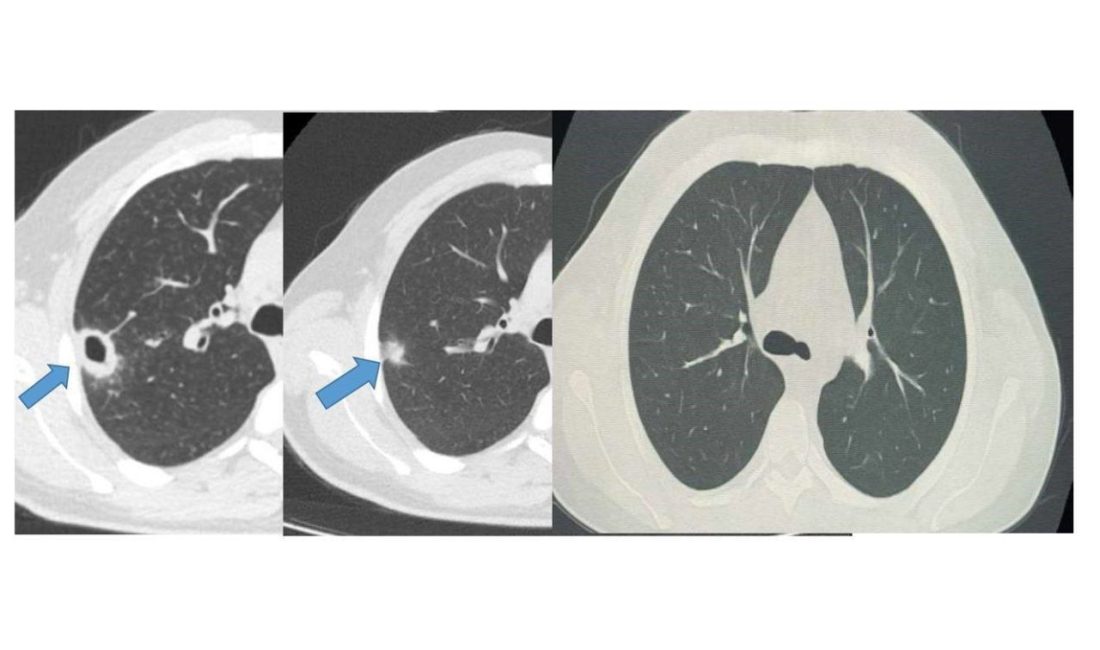

Bayburt Devlet Hastanesine öksürük ve balgam şikayetiyle başvuran 50 yaşındaki hastanın akciğerinde kitle benzeri bir doku tespit edildi. Yapılan tetkikler sonucu ciddi bir hastalık olmadığı belirlenen hasta, erken tanı ve doğru tedavi sayesinde sağlığına kavuştu.

İki haftalık tedavi sürecinin sonunda yapılan kontrollerde lezyonun neredeyse tamamen gerilediği görüldü. Sağlığına kavuşan hastanın taburcu edildiği ve durumunun iyi olduğu öğrenildi.